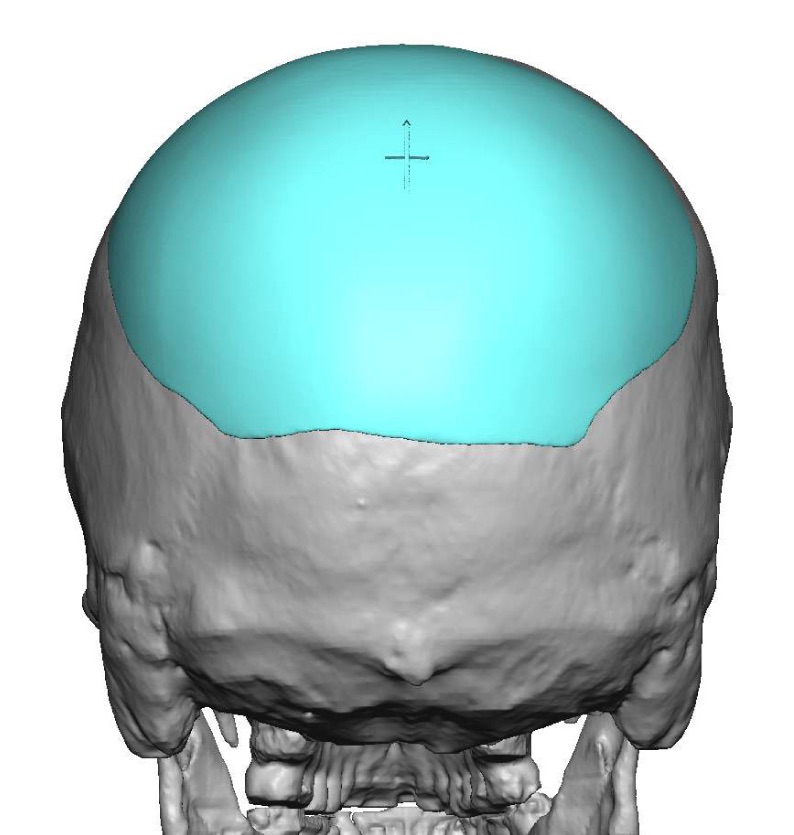

Patient 100

Desire for reshaping of an asymmetric flat back of the head in a shaved head male.

A combined back of the head reshaping procedure was done with a custom skull implant, sagittal ridge reduction and a right temporal muscle reduction.

Desire for reshaping of an asymmetric flat back of the head in a shaved head male.

A combined back of the head reshaping procedure was done with a custom skull implant, sagittal ridge reduction and a right temporal muscle reduction.